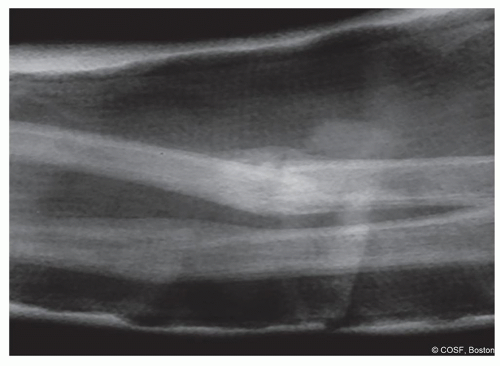

Symptomatic malunion without the potential to remodel (Figure 16.1)

![]() Figure 16-1 ▪ A, Photograph and (B) radiograph of marked malunion with symptomatic block to motion, dysfunction, and pain. (Courtesy of Children’s Orthopaedic Surgery Foundation.) |